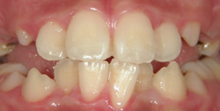

過蓋咬合(かがいこうごう)

上の歯が、下の歯に大きく被さるような深いかみ合わせになっていること。将来的に、

顎関節(アゴ)への負担が大きい為顎関節症を引き起こしやすい事が知られています。 -